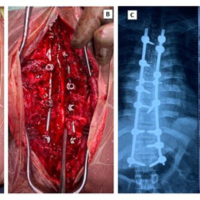

Surgical procedure

After necessary pre-operative investigation and anesthesia clearance (pre-anesthesia checkup) all patients were operated under general anesthesia. Patients underwent posterior decompression and stabilization by pedicel screw fixation to promote neurological recovery and correction of deformity of the spine (Fig. 2). All the patients were operated in the prone position and posterior midline incision was practiced at the affected vertebral levels. Post-operative care involved bed rest, hourly change of posture by log rolling along with physiotherapy of all joints. Intravenous antibiotics were given for 3 days post-operatively followed by a shift to oral antibiotics. The drain was removed 24 h post-operatively followed by a check X-ray. Patients were mobilized on wheel wheelchairs with high Taylor braces after adequate pain relief. Stitches were removed on day 12th post-operatively. Patients were followed up every 4 weeks for 3 months and then every 12 weeks till the past follow-up. The neurological status of each patient was evaluated on initial presentation pre-operatively, at the time of discharge, and during subsequent follow-up visits.